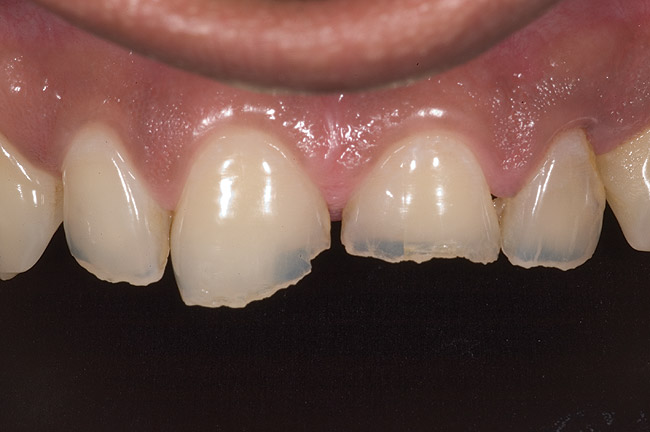

Figure 6  1:1 view demonstrating severe loss of tooth structure due to palatal erosion.

Figure 6